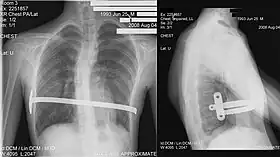

His two-stage procedure, widely known as the Nuss procedure, involves slipping in one or more concave steel bars into the chest, underneath the sternum.[56]

The bar is flipped to a convex position so as to push outward on the sternum, correcting the deformity. The bar usually stays in the body for about two years, although many surgeons are currently moving toward leaving them in for up to five years. When the bones have solidified into place, the bar is removed through outpatient surgery.